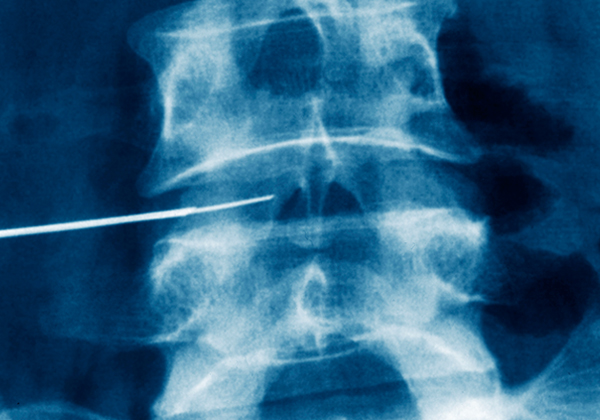

¼ö¼ú ħ»ó¿¡¼ ¾þµå¸° ÈÄ ºÎºÐ¸¶Ãë »óÅ¿¡¼ ¹æ»ç¼± Åõ½Ã ÀåÄ¡¸¦ ÀÌ¿ëÇÏ¸ç °ñÀýµÈ ºÎÀ§¸¦ È®ÀÎÇÑ ÈÄ Àý°³ÇÏÁö ¾Ê°í Á¤ÇØÁø ±æÀ» ÅëÇÏ¿© Á¤È®È÷ ºÎ¼Áø ôÃß »À¿¡ °¡´À´Ù¶õ ÁÖ»ç¹Ù´ÃÀ» »ðÀÔÇÕ´Ï´Ù. ¹Ù´ÃÀÌ Ã´Ãß »À¿¡ Á¤È®È÷ »ðÀÔµÈ °ÍÀ» È®ÀÎÇÑ ÈÄ Ç³¼± ȤÀº ÀÚ¼¼ ±³Á¤À¸·Î ÁÖÀú ¾ÉÀº ôÃß »À¸¦ ¸ÂÃçÁØ ÈÄ¿¡ ôÃß»À ³»¿¡ Ư¼ö Á¦ÀÛµÈ ¾×ü °ñ ½Ã¸àÆ®¸¦ Àû´çÇÑ ¾çÀ¸·Î ¾ÈÀüÇÏ°Ô ÁÖÀÔÇÕ´Ï´Ù. ÁÖ»ç¶ó°í ¸»ÇÒ ¼ö ÀÖ½À´Ï´Ù.